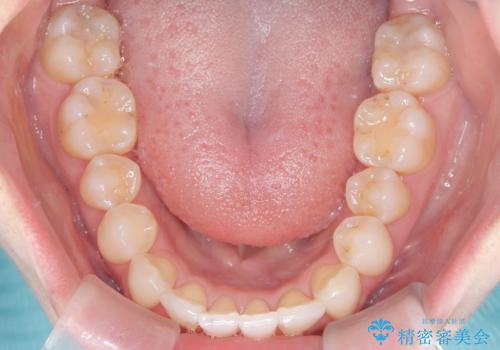

矯正後の後戻りで前歯にガタツキができてしまった インビザラインで改善

- 子どものときにワイヤー矯正をしていたが、後戻りによって前歯のガタツキが気になってきたとのことで来院されました。

アライナー矯正希望だったため、インビザラインによる治療を行いました。

- 7ヶ月